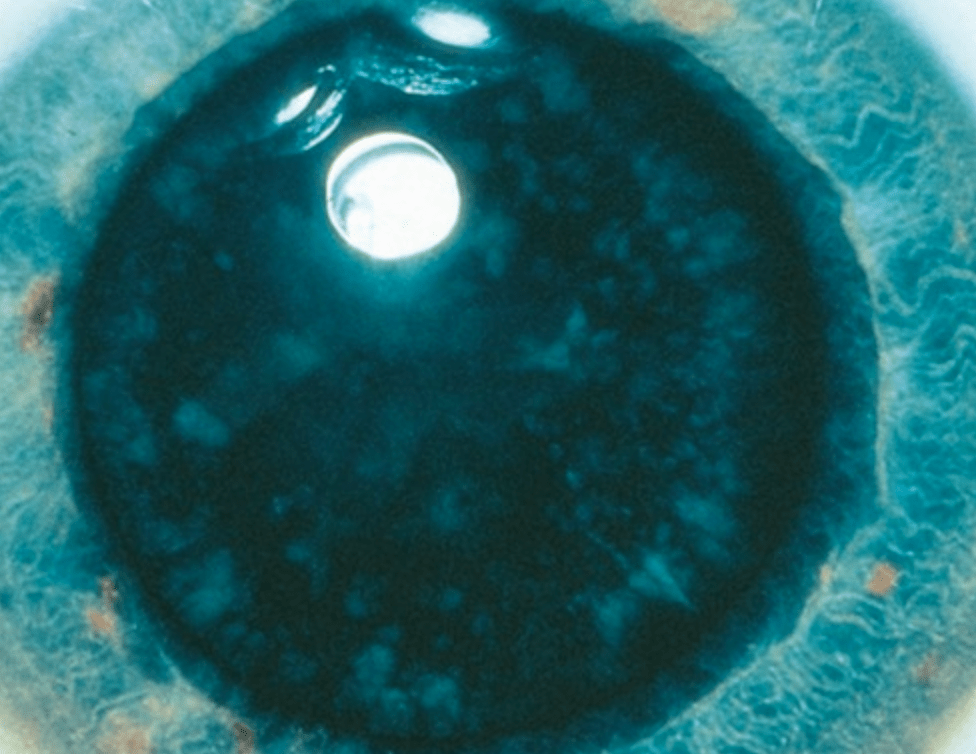

Diagnosis on a test?

Wilson disease - Sunflower cataract

BONUS:

- Autosomal recessive

- Kayser Fleischer ring